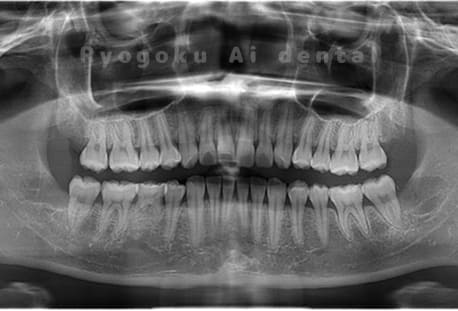

Case04

-

- 原因

- 上顎の親知らず、下顎の水平埋伏の親知らず

- 治療内容

- 上顎の親知らず、下顎の水平埋伏の親知らずを抜歯したケースです。

<リスク・副作用>

手術後は痛み、腫れ、痺れなどの副作用が生じる場合があります。